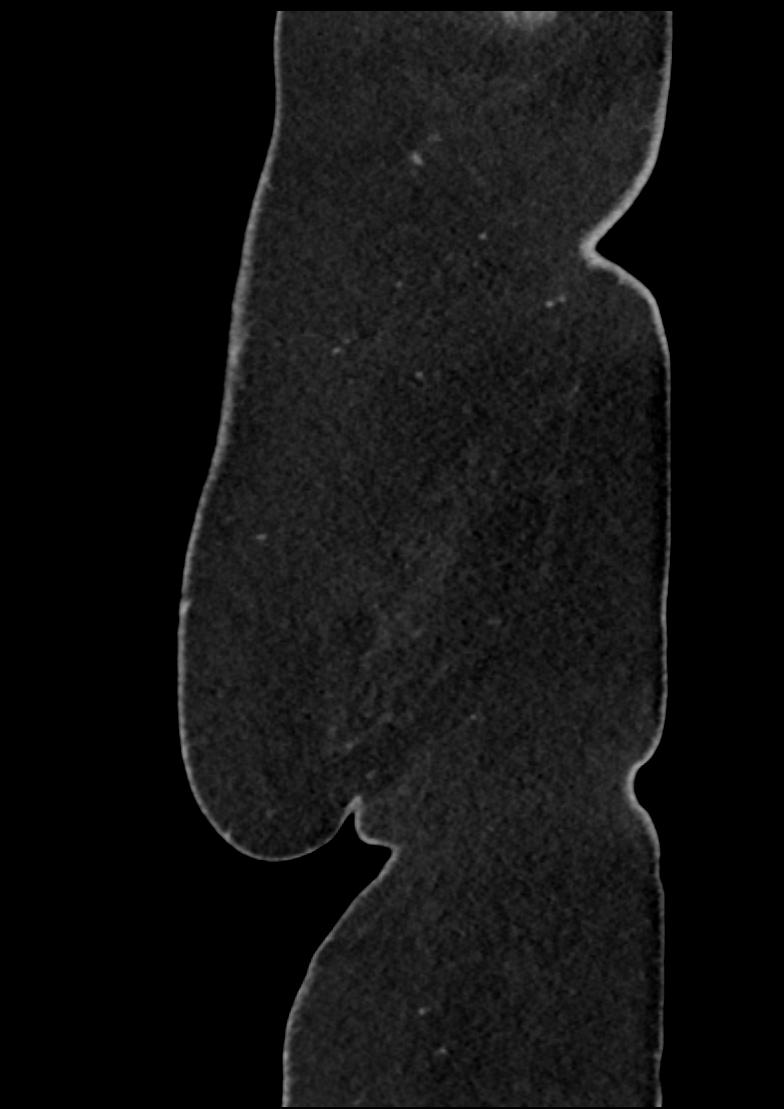

Patient: Padmakumar A. , *1988-04-24, PID: 3000069741773230809

Study Description: CT ABDOMEN

Image Series: Abdomen Sag 3mm [4]